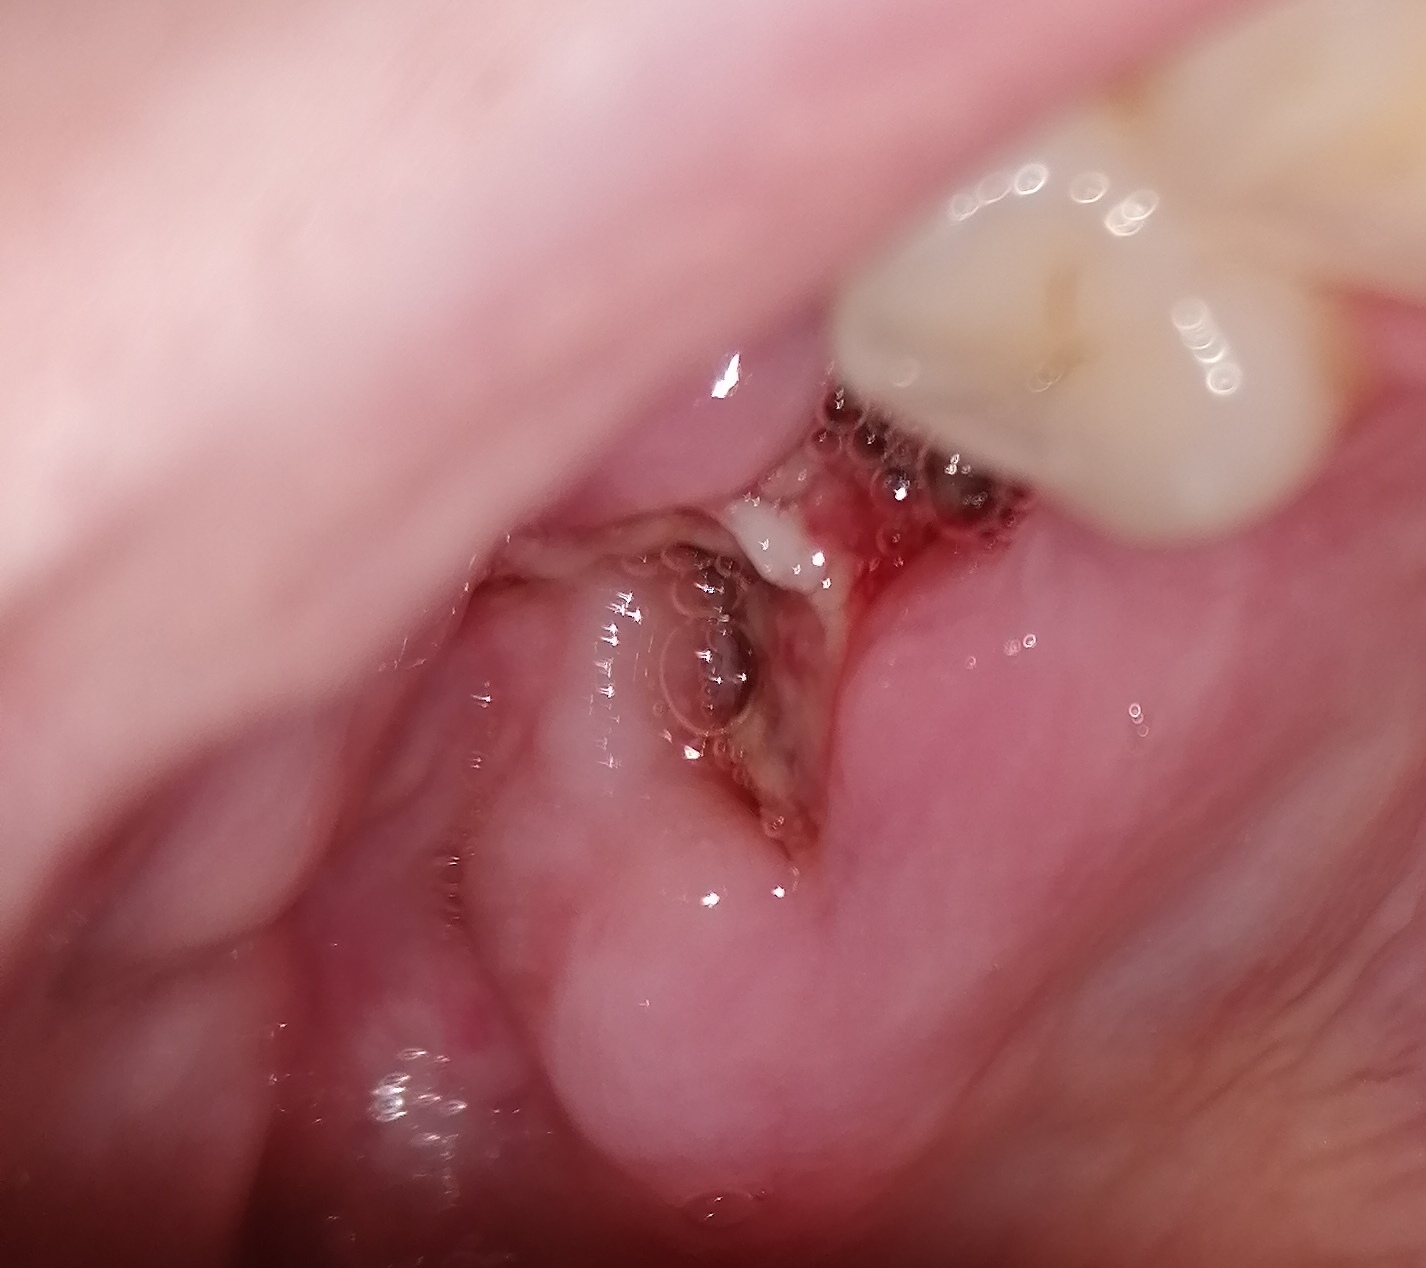

2 achterste kiezen laten trekken, daaronder zat verstandskies die meteen meegenomen is, meteen een uur na het trekken, voelde ik een hard iets met mijn tong, nu 4 dagen later zie ik dat het een stuk kies is?? Of iets anders?? Is dit normaal? Wat moet ik hiermee? Het doet overgings geen pijn. Wel flink gezwelt, wang lijkt wel aan kaak vast te zitten (flinke zwelling in did plooi)

Zie bijlage